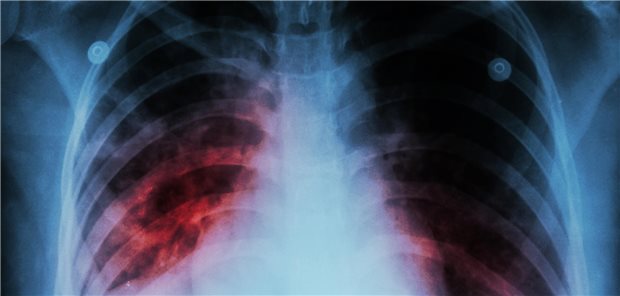

Themenseite Tuberkulose

Themenseite - Tuberkulose

Bakterielle Infektion